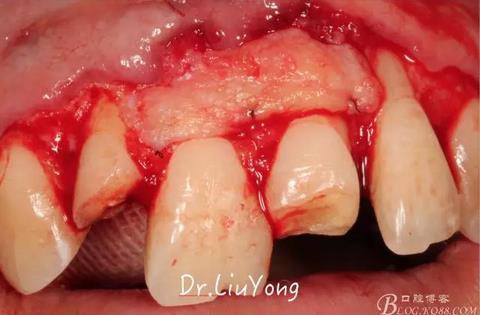

A區(qū)腭側(cè)所移取的上皮下結(jié)締組織瓣,如上圖

將結(jié)締組織瓣縫合固定于受區(qū),如上圖